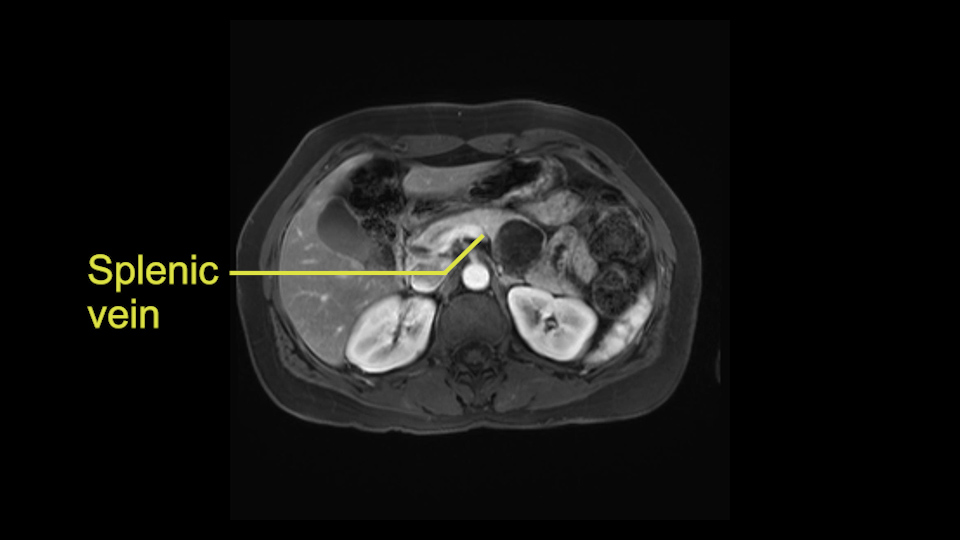

Other slowing down moments with this procedure include dissection of the splenic vein and splenic artery. These are technically challenging moments and important moments where care needs to be taken. Not only to avoid bleeding and injury to the vessels but also to ensure an adequate margin.

The second slowing down moment or consideration I give to a distal pancreatectomy is the anatomy of the portal vein and the splenic artery. And so I look here and the anatomy is pretty straightforward. The splenic vein comes off normally and runs behind the pancreas and I can see the artery superior to that, again coming off in a normal manner from the celiac axis. So those two things, the portal vein and the splenic artery will be taken normally in this procedure.

So first step that we do: mobilize the splenic flexure first to visualize Gerota’s fascia and that would help bring down the colon and expose the pancreatic tail. So now that the pancreas is visible, division of the gastrocolic ligament will come into view. And a window can be created at the inferior edge of the pancreas to slowly lift the inferior edge to expose the splenic vein behind. This is the slow-down moment that I am talking about because the MR shows that there could be contact with the cyst. It’s important to know that to avoid perforation, to avoid rupture of the cyst, because we need to avoid touching the cyst, it is quite a size of 4.3 about 4cm.

I think the splenic vein, once I have slowly teased it off from the cyst and from the retropancreatic parenchyma, I would put a vessel loop around it to serve as a traction. So once you have the vessel loop or probably umbilical tape, to retract or pull the pancreatic parenchyma while we slowly tease it off and try to move superiorly to be able to expose the splenic artery. That is again another slow-down moment because sometimes we think that it is the splenic artery at the superior edge of the pancreas, but it could also be the hepatic artery as it branches from the celiac artery.

So what I would normally do in these patients, I would look at the abutment of any other organs, one, which is here, potentially the adrenal gland and two the small bowel. And two, look at the distance from the vessels which I would normally do in a coronal view. So you can easily measure the distance and third I look at the insertion of the inferior mesenteric vein. Now we can probably also see that on here. Although it's better on a CT scan and it's better on a coronal view, you want to know where the inferior mesenteric vein comes into either the splenic or the SMV, because that is typically a very important slow down moment when you mobilize the lower portion of the pancreas knowing where the inferior mesenteric vein comes in either the splenic vein or the SMV. So those are I think the three most important points for the CT scan.